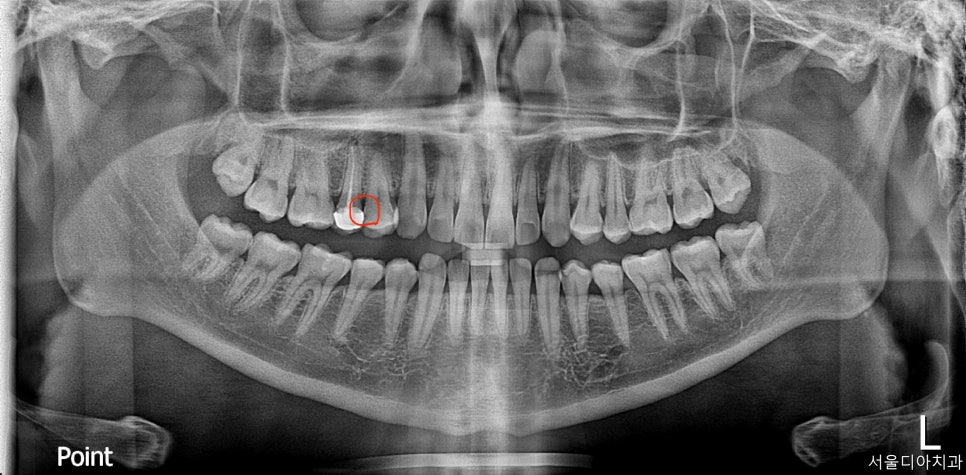

마곡동치과_위 오른쪽 작은 어금니 인접면 충치

충치 부위는 육안 검사와 X-ray 촬영을 통해 꼼꼼하게 확인합니다.

위 사진에 보이는 오른쪽 위의 작은 어금니!

사진 속 빨간 원으로 표시된 부위, 보이시죠?

저기 바로 인접면에 충치가 생긴 위치입니다.

오늘은 바로 그 부위를 ‘당일 인레이 치료’로 해결할 예정입니다.